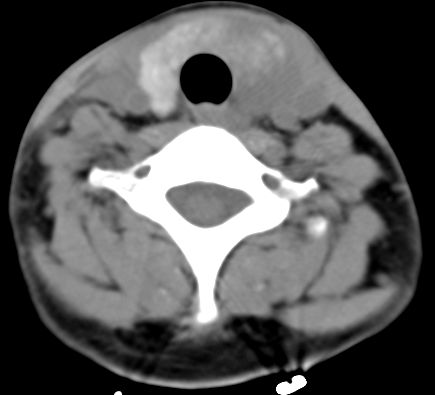

标题: CT9717:F、30Y、颈部左侧包块半年,压痛.患者拒绝作增强。 [打印本页]

标题: CT9717:F、30Y、颈部左侧包块半年,压痛.患者拒绝作增强。

请各位老师帮忙看看左侧甲状腺病灶!

左侧甲状腺见一低密度灶,考虑甲状腺占位。(腺瘤?)

甲状腺弥漫增大,以左叶明显,内见不均匀低密度影,边缘模糊欠清,周围脂肪间隙模糊。

结合病史:考虑亚急性甲状腺炎可能性大。(不知道病人有没有检测tsh t3 t4)

左侧甲状腺及甲状腺狭部弥漫性增大,边缘模糊,未见明确界线.考虑甲状腺炎可能性大.

左侧甲状腺弥满性增大,其内密度均匀减低,气管无受压。周围结构清晰。考虑甲状腺炎可能性大。

甲状腺弥漫增大,以左叶明显,左侧内见不均匀低密度影,边缘模糊欠清,周围脂肪间隙模糊。